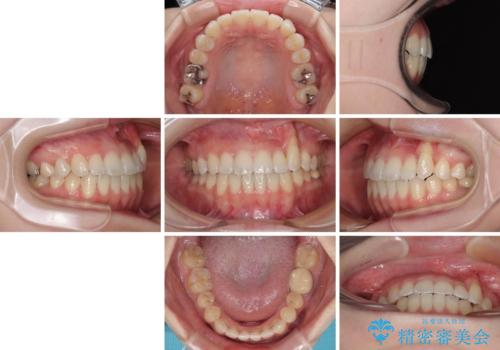

急速拡大装置 狭い上顎骨を拡大してワイヤー装置で八重歯を短期間治療

上顎骨を拡大することで、八重歯やデコボコを歯列に収めることができ、下顎の歯が外に位置していた奥歯の咬み合わせも改善することができました。

スペースも短期間に獲得できるため、1年程度で治療を終えることができました。